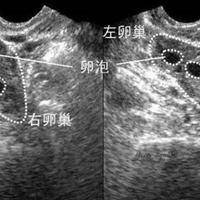

昨天检测还有优势卵泡今天没了是已经排卵了吗?

问题描述;姐妹们,我备孕监测卵泡,昨天B超还看到一个1.9的优势卵泡,医生说明天差不多就该排了,结果今天再去复查,医生说找不到了,盆腔里还有一点点积液。我一下就懵了,这是不是意味着已经排掉了?最佳回答:这确实是已经排卵了的典型信号。排卵过程很快,成熟的卵泡会在瞬间破裂,将卵子释放出来,随后卵泡液被腹腔吸收,B超上就看不到那个饱满的卵泡了。所以,这种情况基本可以判定排卵已经发生,是备孕过程中的一个重...